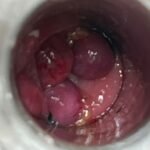

LASER LIAS FOR ANAL FISSURES AND BANDING OF HEMORRHOIDS